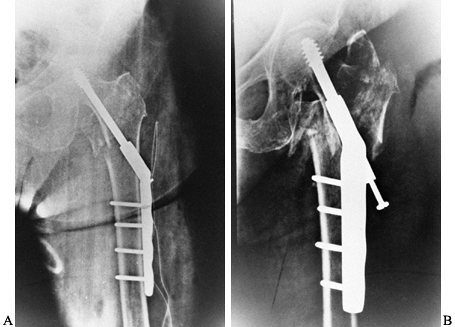

controlled impaction. The sliding hip screw has been our primary means

impaction is anticipated, use short-barrel side plates (Fig. 131.9).

![]() |

Figure 131.9. A: Intertrochanteric hip fracture fixed with sliding hip screw. B: Further impaction. Patient went on to union in this position.